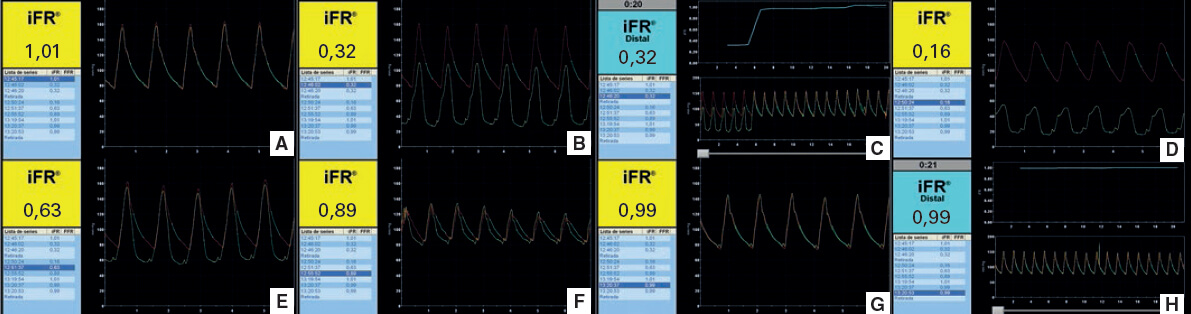

Varón hipertenso y exfumador de 55 años hospitalizado con signos de dolor torácico típico, bloqueo de rama izquierda y niveles normales de troponina. La angiografía reveló enfermedad coronaria de 2 vasos, circunfleja izquierda y coronaria derecha. Esta última se trató con un stent y la circunfleja izquierda mediante intervención guiada por el índice diastólico instantáneo sin ondas (iFR). Después se empleó una segunda guía convencional para dar estabilidad. La figura 1A muestra la angiografía inicial (vídeo 1 del material adicional), la ecualización de las presiones proximal y distal (figura 1B y figura 2A), la angioplastia simple con balón, la medición del gradiente de presión de enclavamiento mediante el iFR (figura 1C y figura 2D), el resultado angiográfico después de la angioplastia con balón (figura 1D), la medición del iFR después de la angioplastia con balón (figura 1E y figura 2E,F) y el resultado final (figura 1F, figura 2G,H y vídeo 1 del material adicional).

La figura 2A muestra la ecualización, un iFR positivo después de la lesión (figura 2B), un cambio brusco del iFR durante la retirada que sugiere estenosis focal (figura 2C), el iFR durante el inflado del balón sin flujo anterógrado (gradiente de presión de enclavamiento según iFR) (figura 2D), el iFR 1 minuto después de la angioplastia (figura 2E), 4 minutos después sin maniobras ni fármacos (figura 2F), el iFR final y el iFR en retirada, respectivamente, después de implantar el stent (figura 2G,H).

Figura 2.

El flujo, todavía bajo (0,63), registrado inmediatamente después de la angioplastia con balón se debió, probablemente, a la microcirculación y al flujo colateral. Esto se explicaría por un mayor flujo después de desinflar el balón de angioplastia derivado de una vasodilatación compensatoria arteriolar. Este flujo aumentado por compensación eleva el gradiente de presión translesional y arroja valores iFR más bajos de lo que cabría esperar después de tratar la lesión. No obstante, el iFR aumentó 4 minutos después (de 0,63 a 0,89), un tiempo razonable para recuperar las condiciones en reposo incluido el tono arteriolar vascular basal, lo cual confirma los buenos resultados fisiológicos de la angioplastia con balón.

En conclusión, los índices fisiológicos en reposo han de emplearse con cuidado y de manera oportuna para evitar sesgos y problemas a la hora de interpretar los resultados.